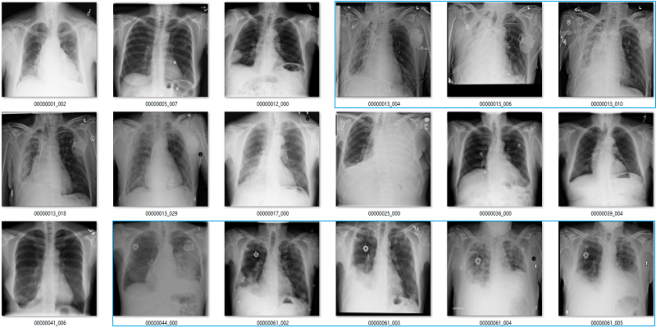

Effusion

In this case, the blue labels mean there is significant lung disease present.

An effusion is fluid in the space around the lung. The list of causes is a mile long, but the two main groups are effusions caused by pleural disease, and those caused by lung disease.

It is not clear to me what it means to identify effusions that exist with significant lung disease. In many of these cases, it is not even really possible to visually identify the effusion, we just know that an effusion must be present so we describe it. See the last three images in the picture above for a good example of this. The main pathology in those cases is consolidation, in my opinion.

I can see value in identifying small, isolated pleural effusions. There are about a half dozen examples of these above, including the first and third images. There isn’t any lung disease to suggest the cause of effusion, which makes the effusion itself significant.

I could also see the benefit in identifying large effusions that might need intervention (like draining them with a needle). The 10th image is an example of this.

So it isn’t really clear to me what this label means. Without a guiding philosophy based in clinical practice, it isn’t very useful.

Pneumothorax

A pneumothorax is when there is air in the pleural space around the lung. This can cause the lung to collapse, and is a pretty serious finding. They can be really subtle on x-rays and are often missed.

At first glance, the labels look good. In these 18 cases, only the one highlighted in orange is a bit questionable, and that may just be because I am not looking at the image in diagnostic conditions.

But the green boxes are a problem. These are cases of pneumothorax where the patient has already been treated with a chest drain. There are two issues here:

- This isn’t a medically important problem. We want to avoid missed pneumothoraces, and by definition these have not been missed.

- If so many of the images have chest drains, an AI system will probably learn to identify chest drains instead of pneumothoraces. It is entirely likely that the majority of image batches the model sees will contain no pneumothorax without a chest drain.